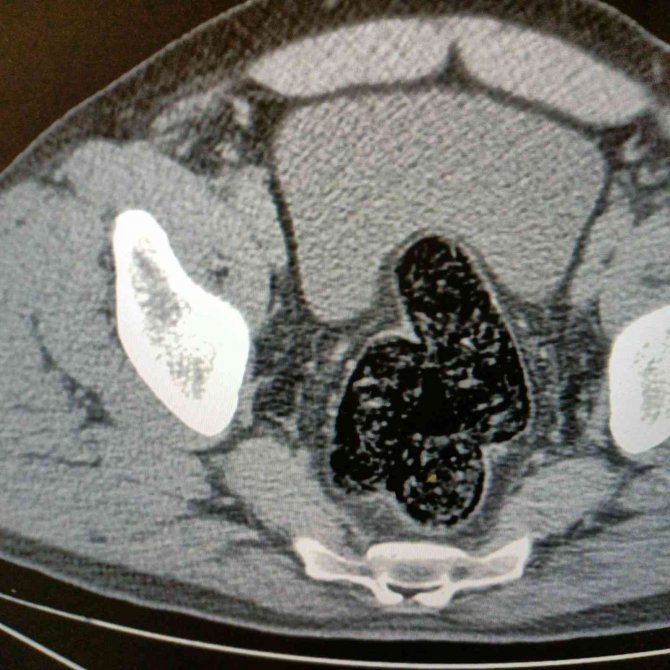

Ağrı'da, uyuşturucu veya uyarıcı madde ticareti yapan veya sağlayan kişilere yönelik yapılan çalışmalar neticesinde Bölge Trafik Uygulama Noktası'nda durdurulan 04 T 3052 plakalı araçta yolculuk eden İran uyruklu bir kişide arama yapıldı. Yapılan aramalar sonucunda, şahsın pantolonunun cep kısmında iki parça halinde şeffaf poşete sarılı vaziyette 10.17 gram gelen metamfetamin maddesi ele geçirildi. Şahsın devam eden işlemlerinde gözlerindeki kızarıklık, yemek ihtiyacı istememesi, aşırı tedirgin davranışlar sergilemesi üzerine yapılan iç beden muayenesi neticesinde röntgen vasıtasıyla makat ve bağırsak kısmında uyuşturucu kapsülleri olduğu tespit edildi. Doğal yöntemlerle şahıstan 12 adet kapsül toplam daralı ağırlığı 345.19 gram gelen metamfetamin ele geçirildi. Şahsın üzerinden ve iç bedeninden toplamda 355.36 gram uyuşturucu madde ele geçirildi.